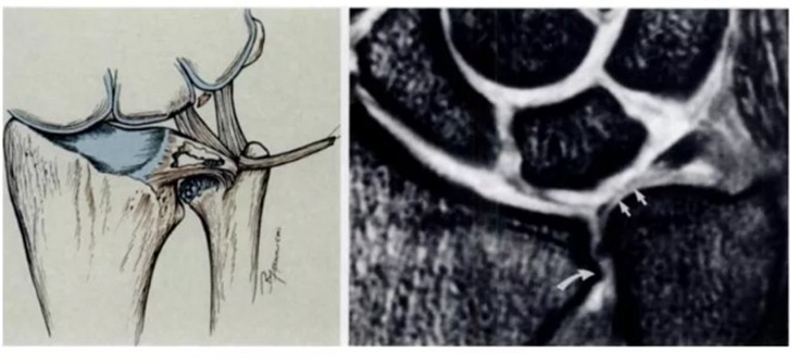

三角纤维软骨复合体(TFCC)是手腕最重要的纤维软骨-韧带复合结构,位于腕关节尺侧,分隔尺腕和远侧尺桡关节。常被称为是腕关节的“半月板”。

TFCC由以下韧带和纤维软骨组成:固有三角纤维软骨(TFC)、背侧桡尺韧带(DRUL)、掌侧尺韧带(PRUL)、尺三角韧带(UTL)、尺月韧带(ULL)、月三角韧带(LTL)、尺侧腕伸肌腱(ECU)鞘、尺侧副韧带(UCL)及半月板类似体(MH)。

固有三角纤维软骨

半月板同系物是关节盘远侧增厚的尺侧副韧带纤维形成半月板类似体,与关节盘共同起于尺骨背侧靠近尺骨的边缘,有尸解证实其附着于豌豆骨。

半月板同系物

血供

TFCC的周边约20%的区域(桡侧缘除外)有血供,中心约80%的区域无血供。这就决定了TFCC不同部位损伤后具有完全不同的愈合能力,同时也提示不同的分型需采取不同的治疗方式。早期明确损伤的性质以及撕裂的部位对临床治疗方法的选择具有关键性指导意义。